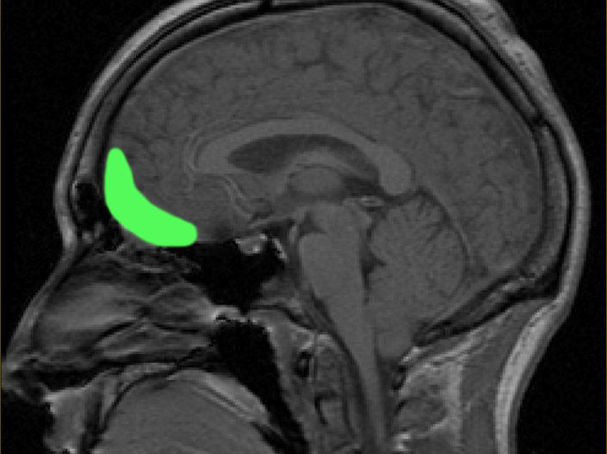

In 1848, John Harlow first described the case of a 25-year-old railroad foreman named Phineas Gage. Gage was a "temperate" man: hardworking, polite, and well-liked by all those around him. One day, Gage was struck through the skull by an iron rod launched in an accidental explosion. The rod traveled through the prefrontal cortex of his brain. Remarkably, he survived with no deficits in his motor function or memory. However, his family and friends noticed major changes in his personality. He became impatient, unreliable, vulgar, and was even described as developing the "animal passions of a strong man." This was the first glimpse into the important role of the prefrontal cortex in personality and social behavior (David, 2009; Thiebaut de Schotten, 2015; Benjamin, 2018).